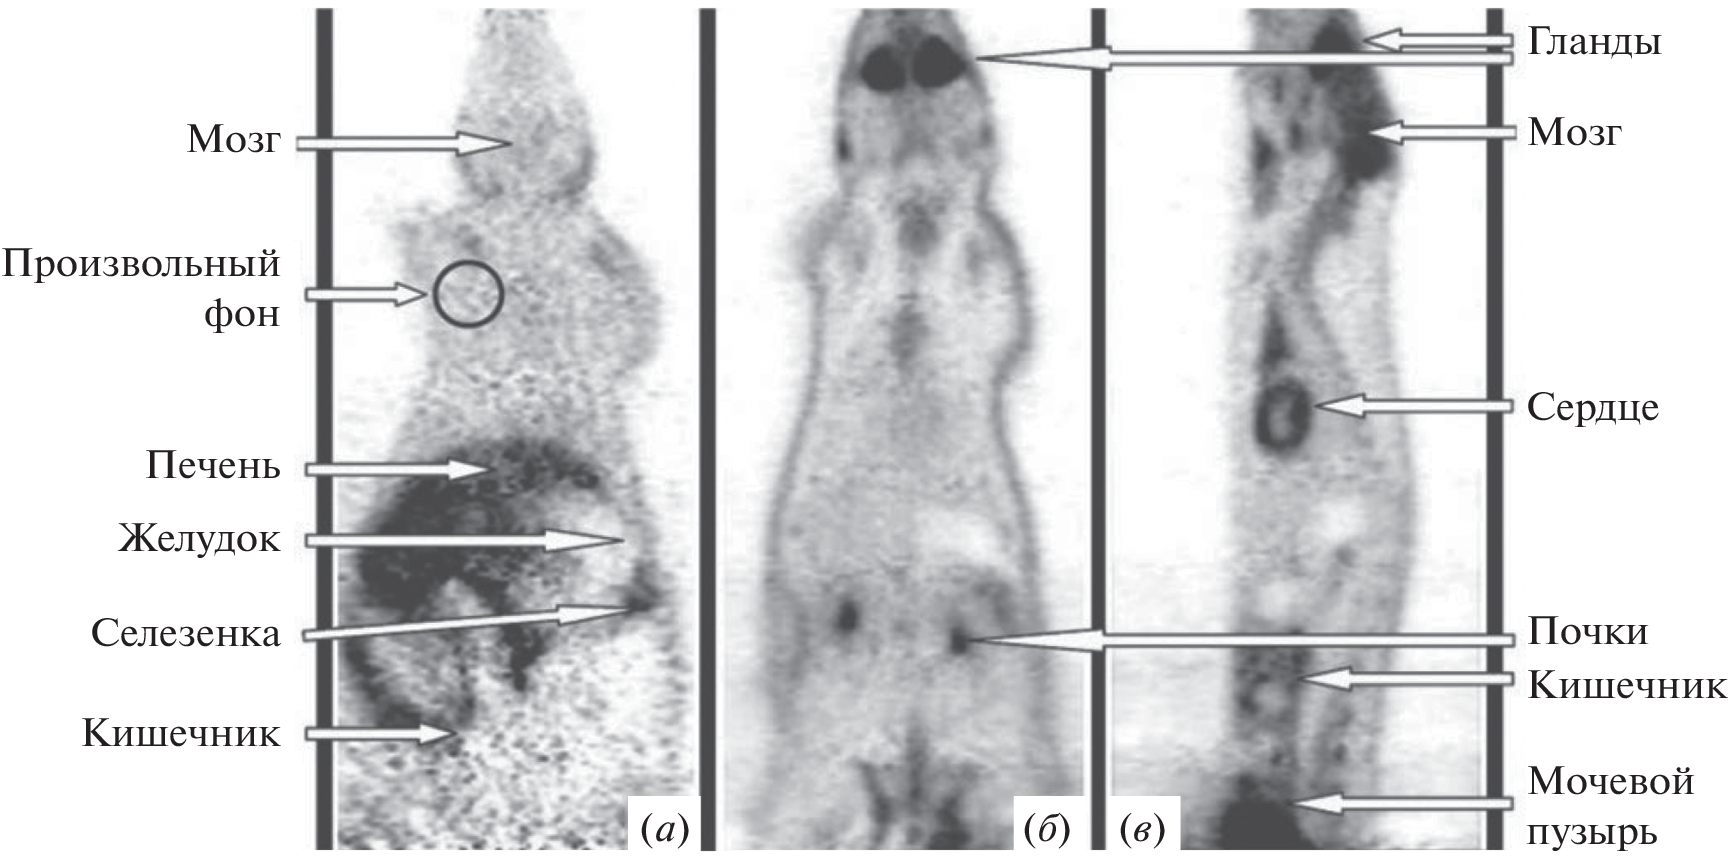

To date, the most common drug for the diagnosis of cancer tumors is [18F]-fluorodeoxyglucose, an radiopharmaceuticals for positron emission tomography diagnostics using the fact of increased glucose metabolism by cancer cells. At the same time, there are a number of cases where an approach based on glucose derivatives is not applicable. In many cases, inflammation or other benign processes are indistinguishable from tumor formations. For such cases of non-specificity of oncologies to glucose (not only tumor cells, but also healthy cells actively consume [18F]-fluorodeoxyglucose), the use of other metabolic pathways is required, which, in the case of a specific tumor in this organ, will be specific to the radiopharmaceuticals used.